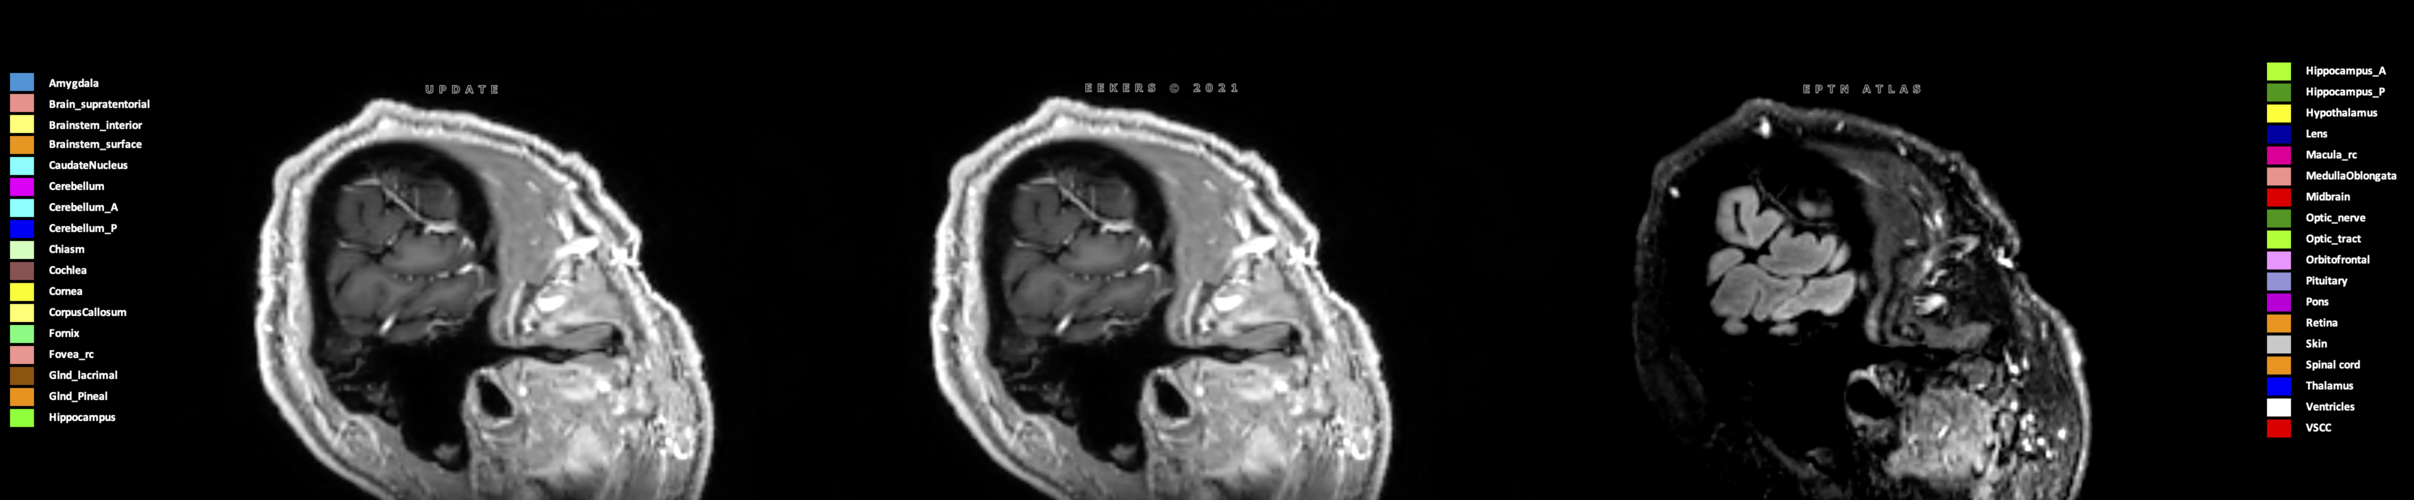

Eekers et al. have published an international neurological atlas for contouring of organs at risk in consensus with the European Particle Therapy Network (EPTN) in 2018 and an update in 2021. The purpose of this consensus atlas is to decrease inter- and intra-observer variability in delineating OARs relevant for neuro-oncology.

Three-dimensional delineation of the 25 consensus OARs for neuro-oncology are shown on CT (WW/WL 120/40, 3000/600), 3T MR images, (T1Gd, T2FLAIR 1mm) and 7T MR (MP2RAGE 0.7 mm). All are presented in transversal, sagittal and coronal view.

Eekers D, Di Perri D, Roelofs E, Postma A, Troost EG. EPTN International Neurological Contouring Atlas - 2021 Update CancerData, 2021. doi:10.17195/candat.2021.02.1